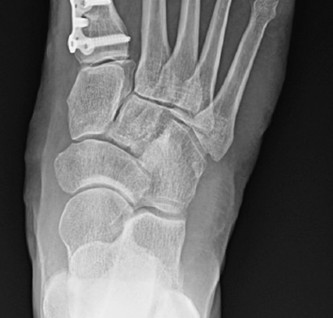

Figure 4: Intraoperative image demonstrating a distal metatarsal osteotomy (e.g., Chevron) with planned screw fixation. -

Shaft Osteotomies (e.g., Scarf, Ludloff): Used for moderate to severe deformities (IMA > 16-18°).

- These are more powerful corrections, allowing for greater translation, rotation, and plantarflexion/dorsiflexion adjustments.

- Fixation typically involves two screws.

Figure 5: Radiographic depiction of a stabilized osteotomy (e.g., Scarf), demonstrating the correction of the IM angle and use of internal fixation. -

Proximal Metatarsal Osteotomies (e.g., Opening/Closing Wedge): Used for severe deformities or when significant IMA correction is needed.

- Often require plate and screw fixation or staples.

Key Consideration: After the osteotomy and translation, ensure the first MTP joint is stable and congruent. The goal is to achieve an HVA of 5-10° and an IMA of <9-10°.